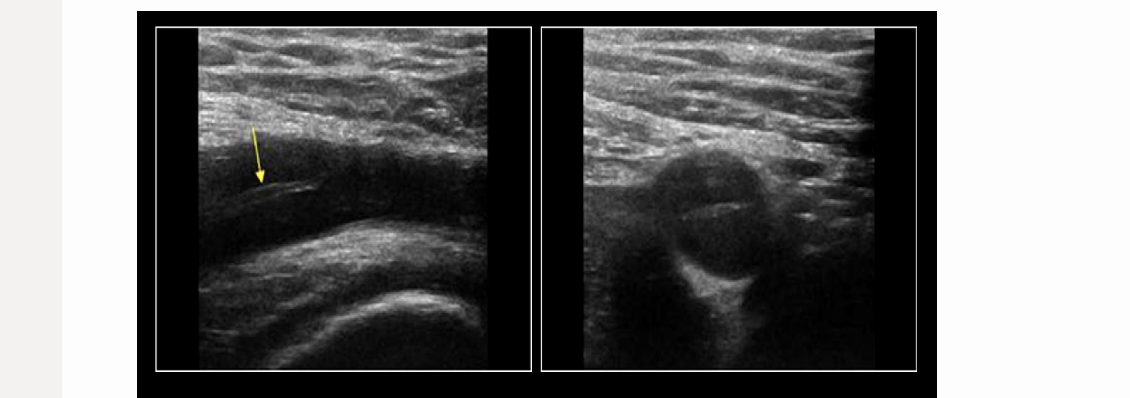

a 30 yo male has persistent right calf pain w/exercise. this is the right popliteal artery w/foot in neutral + flexed position

.

a) Buerger disease

b) anterior compartment syndrome

c) popliteal entrapment

d) Leriche syndrome